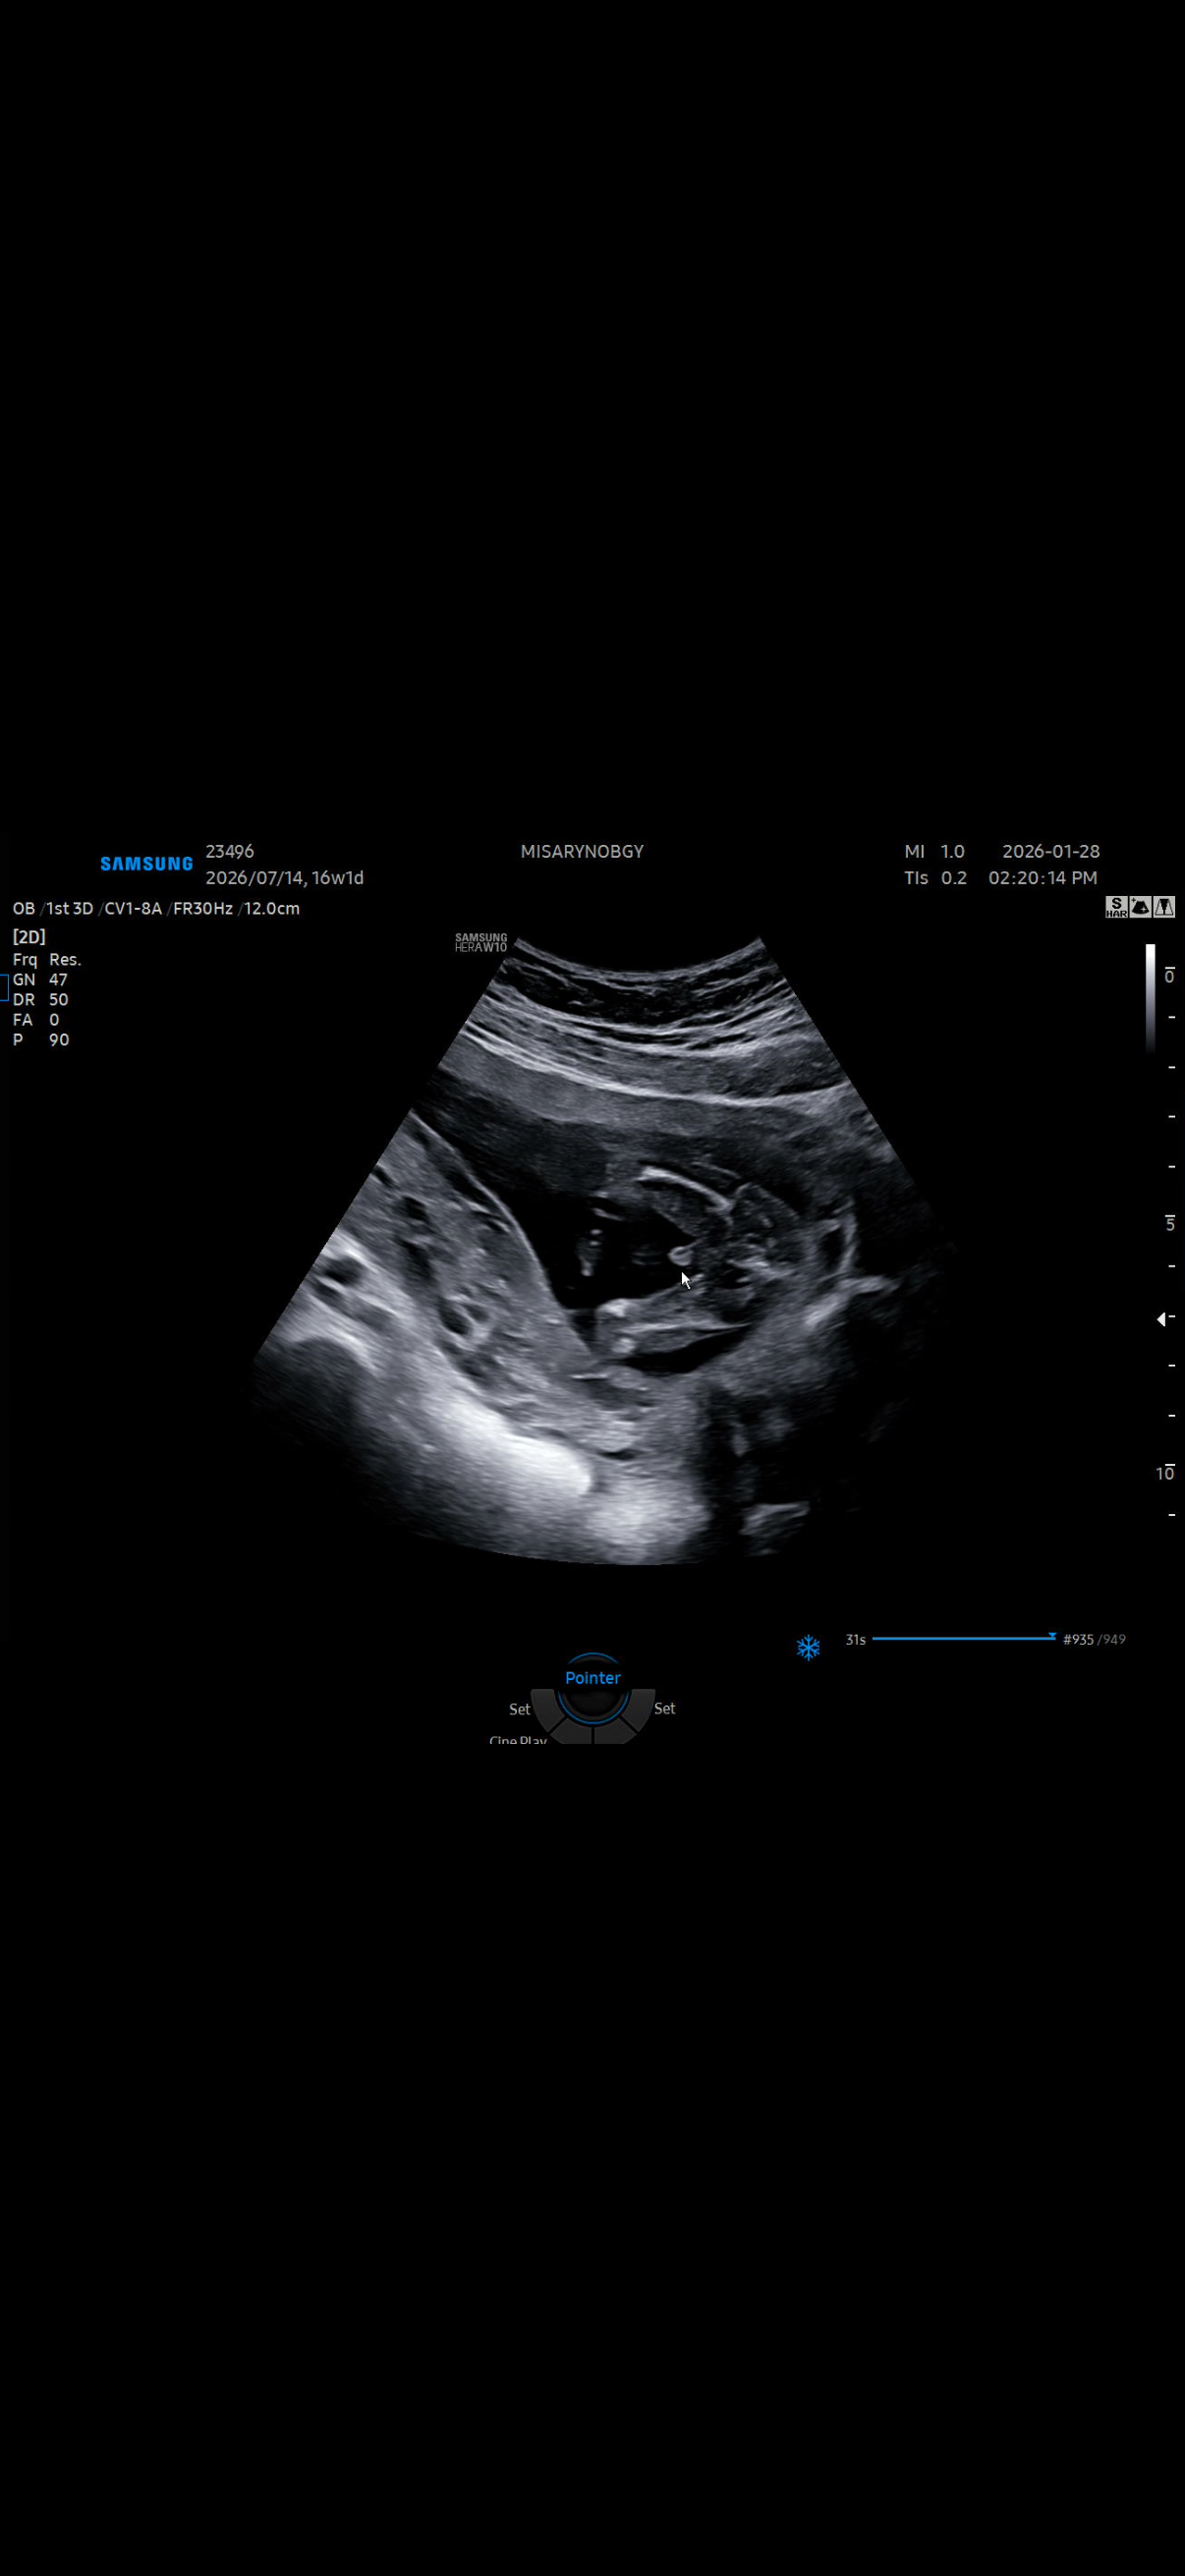

확신의 아들^^

16주1일입니다^^ 반전은 없겠죠